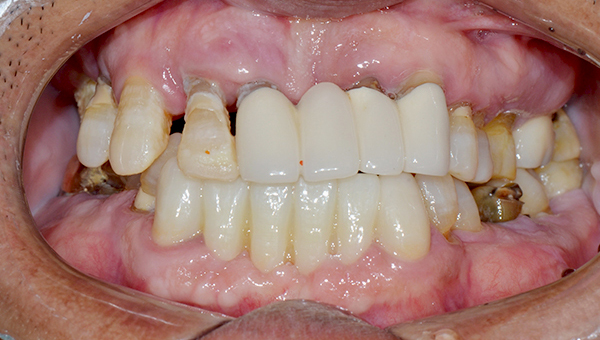

치료사례임플란트

강*란 임플란트 시술 사례

전체 임플란트

2025.02.07

치료 전

2025.08.19

치료 후